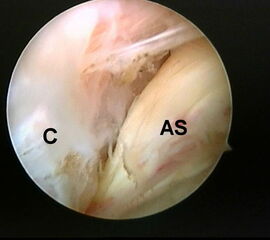

Abbildung 5-7, Video 2

Zunächst wird die Bursektomie (Abb. 5: gerötete Bursa subachillea; C=Calcaneus, B=Bursa, AS=Achillessehne) mit der Radiofrequenzsonde durchgeführt und die Haglundexostose dargestellt. Alternativ kann die Bursektomie mit einem Shaver durchgeführt werden. Hierbei sollte der Ansatz der Achillessehne kaudal einsehbar sein (Abb. 6: C=Calcaneus, AS=Achillessehne) und unbedingt die gesamte mediolaterale Ausdehnung der posterioren Calcaneusfläche erfasst werden (Abb. 7). Häufig liegen Anteile der Exostose weit medial und/oder lateral und werden übersehen.